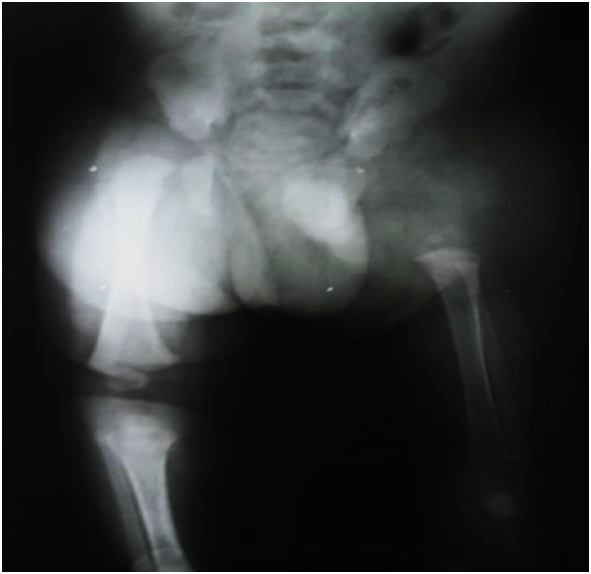

Se realiza estudio radiológico confirmando ectrodactilia en mano derecha (figura 4) y hallazgo ecográfico de ausencia de femur izquierdo (figura 5). A las 48 horas egresan madre y neonato por evolución satisfactoria, con evaluacion ambulatoria por servicio de traumatología donde sugieren colocación de expansor en el muslo afectado y posteriormente sustituirlo por una prótesis femoral definitiva. De igual manera se realizó en etapa neonatal, estudio citogenético en sangre periférica el cual reporto cariotipo masculino normal (46, XY).

Las clasificaciones establecidas de anomalías congénitas del fémur se concentran en el examen detallado de las radiografías. Las clasificaciones más conocidas en la literatura inglesa son las de Aitken (1959) y Amstutz y Wilson (1962). La clasificación de Aitken se concentra en la presencia o ausencia de continuidad cartilaginosa del fémur proximal y el desarrollo de la articulación de la cadera. (11) En ella los pacientes se clasifican en cuatro grupos (A-D), desde un defecto leve (tipo A) con fémur corto pero cabeza femoral y acetábulo normales, hasta casos muy severos (tipo D) en los cuales tanto cabeza femoral como acetábulo están ausentes y el fémur es muy corto y curvado. Esta clasificacion tiene implicaciones pronósticas y terapéuticas. De forma general, se acepta que los alargamientos son posibles en los tipos A y B. (12) La clasificación de Amstutz y Wilson intenta un desglose detallado de todos los tipos anatómicos desde un grado leve de hipoplasia femoral hasta la ausencia subtotal del fémur. Hamanishi (1980) definió cinco tipos que con subtipos dan 10 grupos de pacientes. (11) descritos como siguen: Tipo I, hipoplasia simple del fémur: (a) forma normal; (b) eje ligeramente angulado y engrosamiento cortical. Tipo II, fémur corto con eje angulado: (c) marcada angulación lateral y engrosamiento cortical resultante de defecto de osificación subtrocantérico transversal; (d) disminución del ángulo del eje del cuello. Tipo III, fémur corto con coxa vara: (e) con eje recto, coxa vara estable con marcado engrosamiento cortical en el trocánter menor; (j) con eje angulado, progresivo coxa vara con corteza engrosada. Tipo IV, fémur proximal ausente o defectuoso (g) cuello y trocánter ausentes o fibrosos, migración del eje superior, la distancia corta entre la cabeza del eje y el defecto de osificación transversal diafisaria; (h) cuello ausente con trocánter cabeza femoral pequeños que se conectan directamente al eje cónico; (i) todo el fémur proximal está ausente. Tipo V.(j) fémur ausente o rudimentario que se osifica más tarde, categoría donde se ubicaría el caso clínico descrito (13).